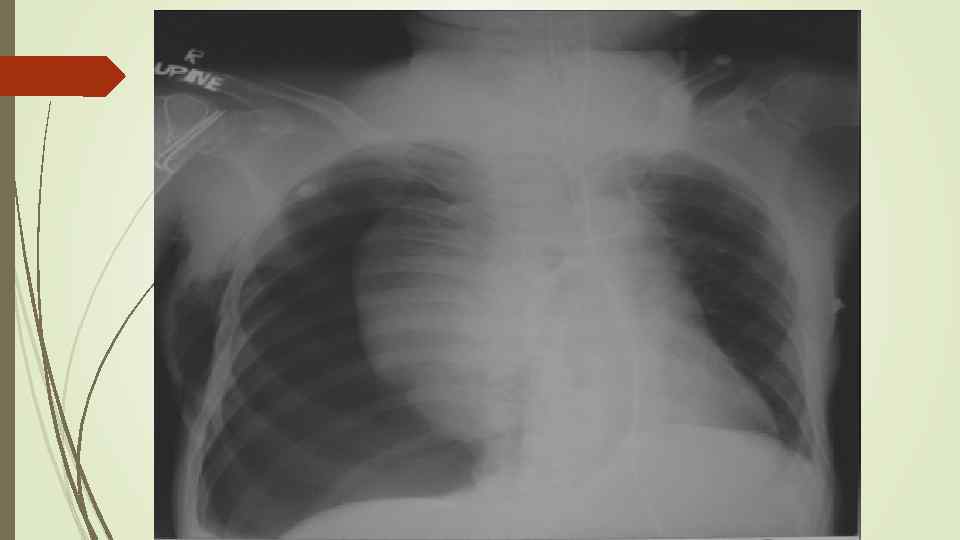

Плевральный выпот Скопление жидкости в плевральной полости (исключение гемоторакс, хилоторакс, пиоторакс) Транссудат Экссудат Плеврит

Плевральный выпот Скопление жидкости в плевральной полости (исключение гемоторакс, хилоторакс, пиоторакс) Транссудат Экссудат Плеврит

Рентгенологическое исследование: свободный газ в плевральной полости (участок просветления, лишенный легочного рисунка, расположенный на периферии легочного поля, на фоне пневмоторакса отчетливее, чем обычно, видны детали костного скелета грудной клетки) поджатое лёгкое, степень спадения которого зависит от величины пневмоторакса при напряжённом пневмотораксе средостение смещается в здоровую сторону.

Рентгенологическое исследование: свободный газ в плевральной полости (участок просветления, лишенный легочного рисунка, расположенный на периферии легочного поля, на фоне пневмоторакса отчетливее, чем обычно, видны детали костного скелета грудной клетки) поджатое лёгкое, степень спадения которого зависит от величины пневмоторакса при напряжённом пневмотораксе средостение смещается в здоровую сторону.